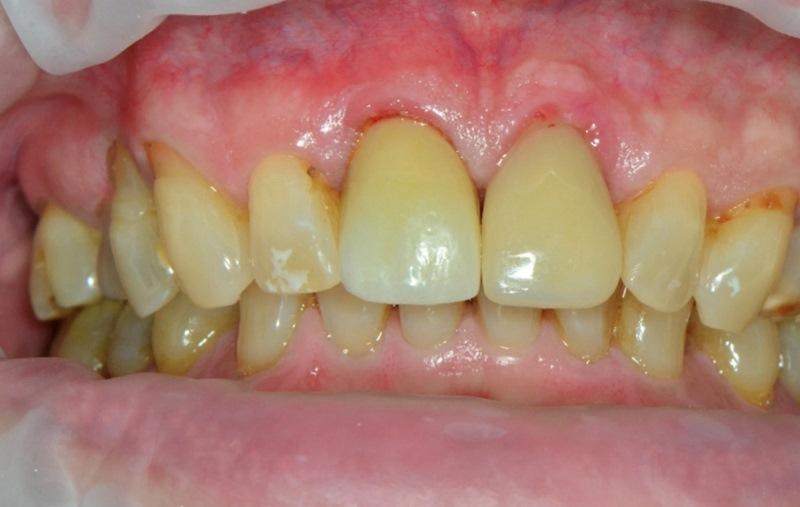

Через 4 месяца после установки имплантата пациент явился для контроля заживления и оценки остеоинтеграции. После снятия ретейнера Essix мягкие ткани вокруг индивидуального формирователя десны без признаков воспаления (Фото 8). Снятие формирователя десны выявило хорошо сформированный десневой манжет без воспалительных явлений (Фото 9). Показатель ISQ 72 подтвердил успешную остеоинтеграцию и готовность к протезированию.

Фото 8. Индивидуальный формирователь десны после завершения этапа интеграции имплантата.